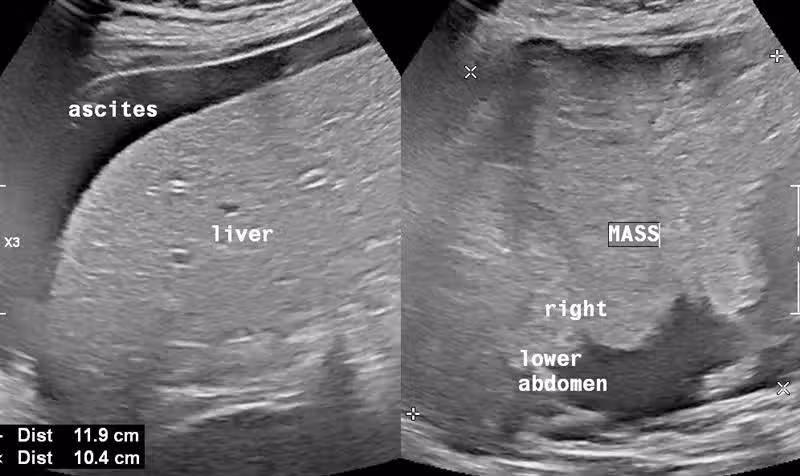

醫師謝文斌在臉書發文分享案例,一位50歲女子上周三因肚子悶痛前往社區衛生所看診,不過並非劇烈痛,是一種說不上來的不舒服。